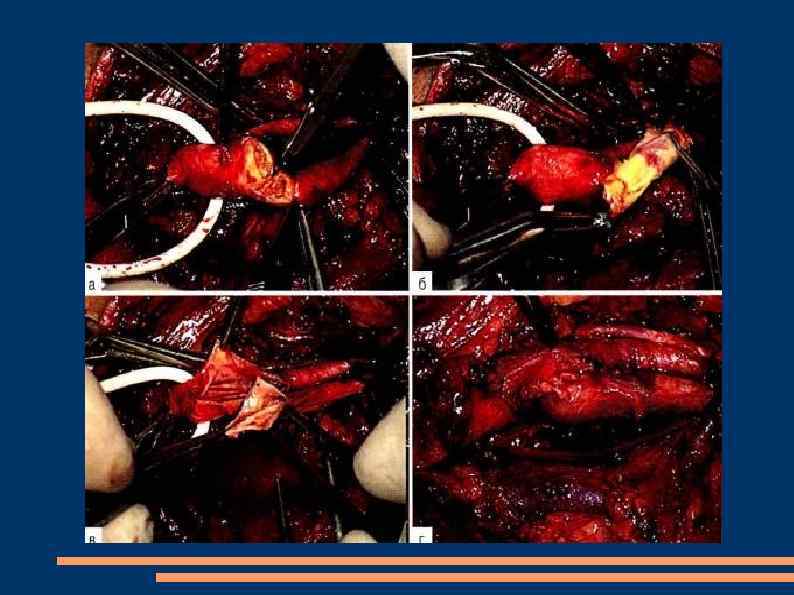

Хирургическое лечение окклюзии аорто-бедренного сегмента Операции прямой реваскулризации: Эндартерэктомия - удаление субстрата вызывающего окклюзию через миниразрез артерии с последующим его ушиванием сосудистым швом или с применением аутовенозной или синтетической "заплаты" Протезирование - замена пораженного участка сосуда на синтетический протез или аутовену Шунтирование Эндоваскулярная ангиопластика со стентированием

Эндартерэктомия Полуоткрытый способ Закрытый Открытый эверсионный

Открытая эндартерэтомия

Эверсионная эндартерэктомия